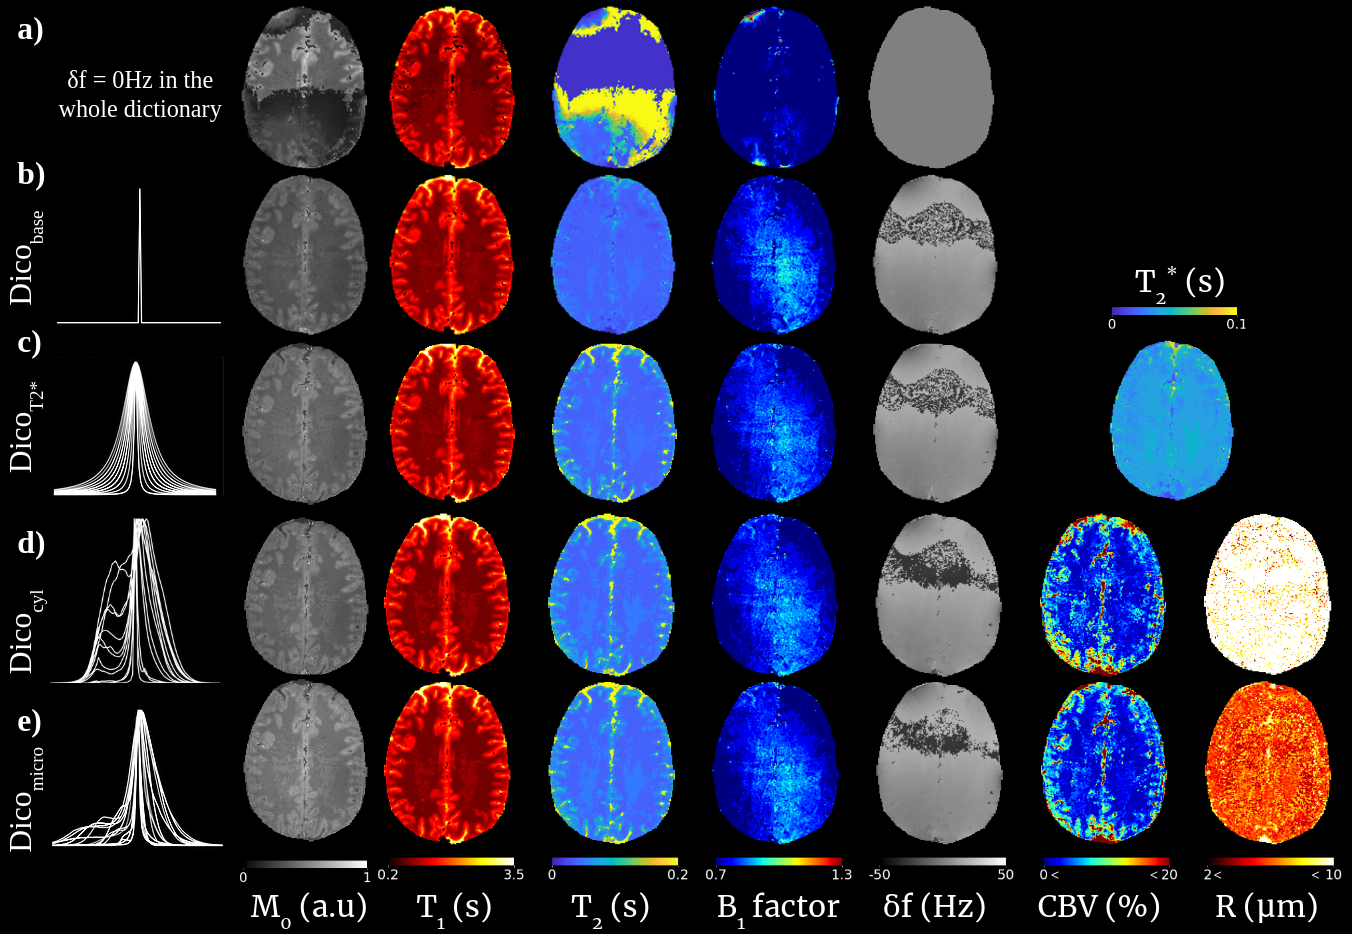

Figure 7 shows results obtained with the MRvF-bSSFP sequence in another subject. Different dictionaries including increasingly realistic frequency distributions were used for the reconstructions. This highlights the sensitivity of the sequence to the frequency dimension, showing that T1 and T2 maps are not well estimated with unique values. T2* maps and better T2 estimates are obtained when considering Lorentzian distributions. CBV and R values are obtained when considering vascular distributions with differences between the cylinder and realistic microscopy distributions. A clear contrast between CBV values in GM and WM can be observed. Larger CBV and R values are also found in large blood vessels such as the SS. Using realistic microscopy distributions, R values are lower than using cylinders and in the range of physiological values.